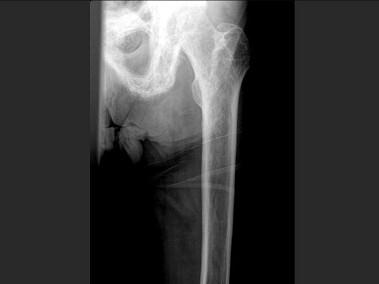

问题 男,60岁,左股骨痛1年余,结合图像,最可能的诊断是?(?)

选项 A.骨纤维异常增殖症 B.Paget病 C.髋关节结核 D.股骨头缺血坏死 E.化脓性骨髓炎

答案 B